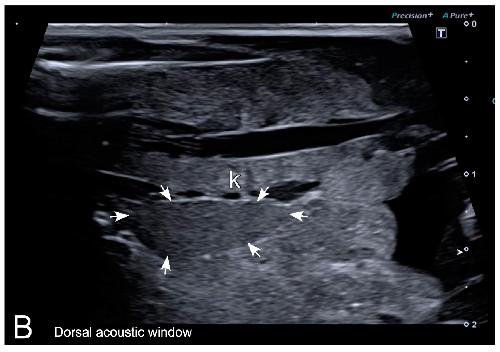

Sex Determination in Two Species of Anuran Amphibians by Magnetic Resonance Imaging and Ultrasound Techniques., Ruiz-Fernández MJ, Jiménez S, Fernández-Valle E, García-Real MI, Castejón D, Moreno N, Ardiaca M, Montesinos A, Ariza S, González-Soriano J., Animals (Basel). November 18, 2020; 10 (11):